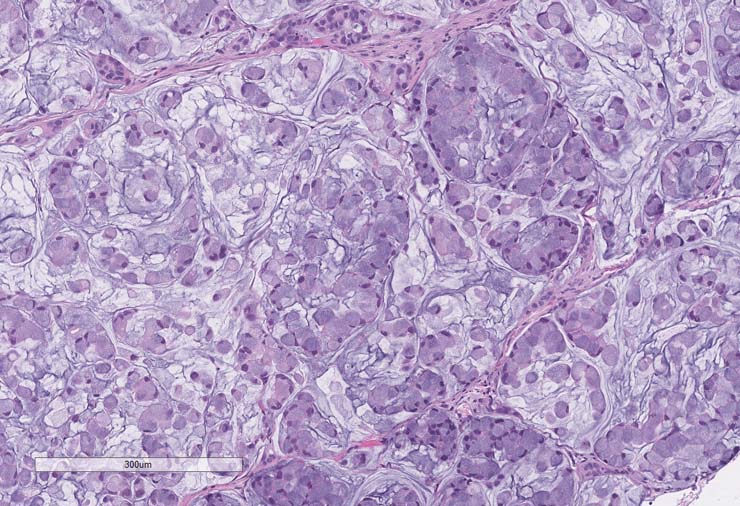

P0, P1 pathology consistent with adenocarcinoma. P2 pathology consistent with mucinous adenocarcinoma.

P0 tumor F240 for PDX model TM00351 stained for H&E.

P1 tumor F239 ID003 for PDX model TM00351 stained for H&E.

P2 tumor F239 ID011 for PDX model TM00351 stained for H&E.